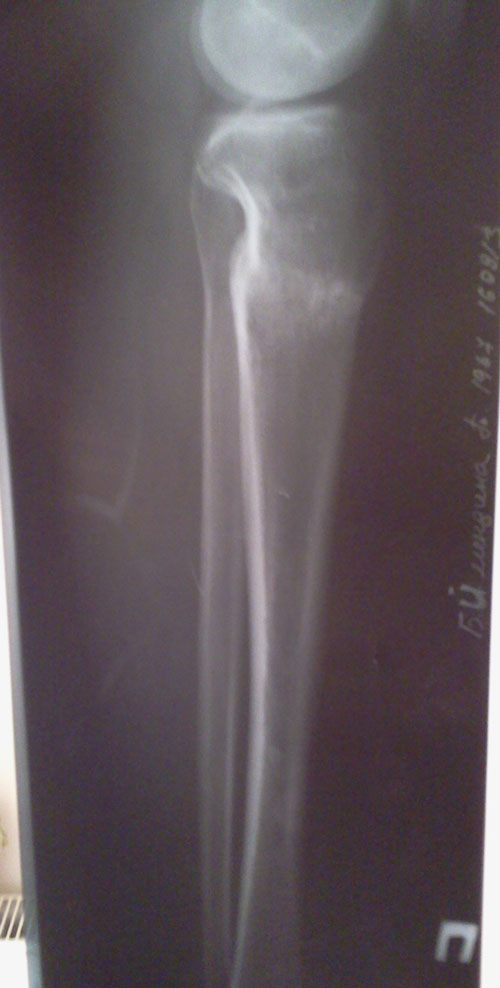

- Диагноз: О-образная деформация нижних конечностей

Дата операции 10.04.2013г.

Дата снятия аппаратов 26.07.2013г.

Срок лечения 104 дня.